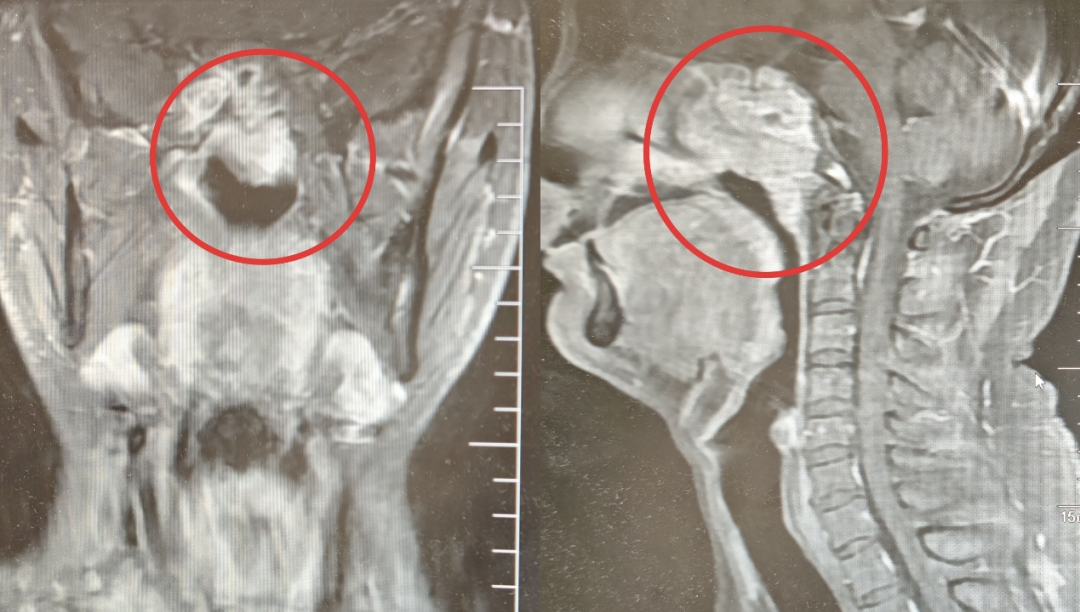

▲小黄的CT影像

第二步:初见成效治疗起效非常直观。在第1个周期化疗结束后,小黄第二次来医院时,自己都感觉到了明显的变化:头痛大幅减轻,往右看的时候,眼球也能稍微转过去一些了。复查的CT印证了他的感受:肿瘤已经开始退缩。 随着治疗周期稳步推进,小黄的右眼活动功能基本恢复正常,头痛也彻底消失了。

▲患者之前前后CT影像